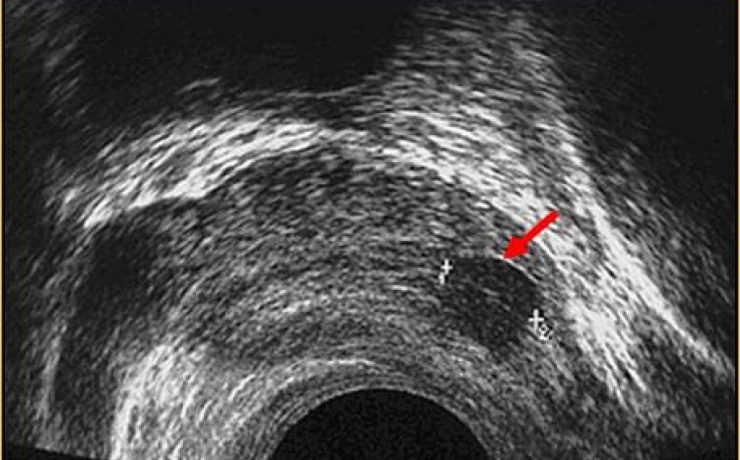

Aspectos ultrasonograficos del riñón

Los riñones órgano parque se encuentra en ambos lado de la columna vertebral dorso-lumbar, se sobreponen parcialmente en la parrilla costal baja y se sitúan retroperitoneales entra la 3ra y 6ta vertebra lumbares. Se dividen para su estudio en corteza, medula y seno; La densidad de su parénquima (medula y